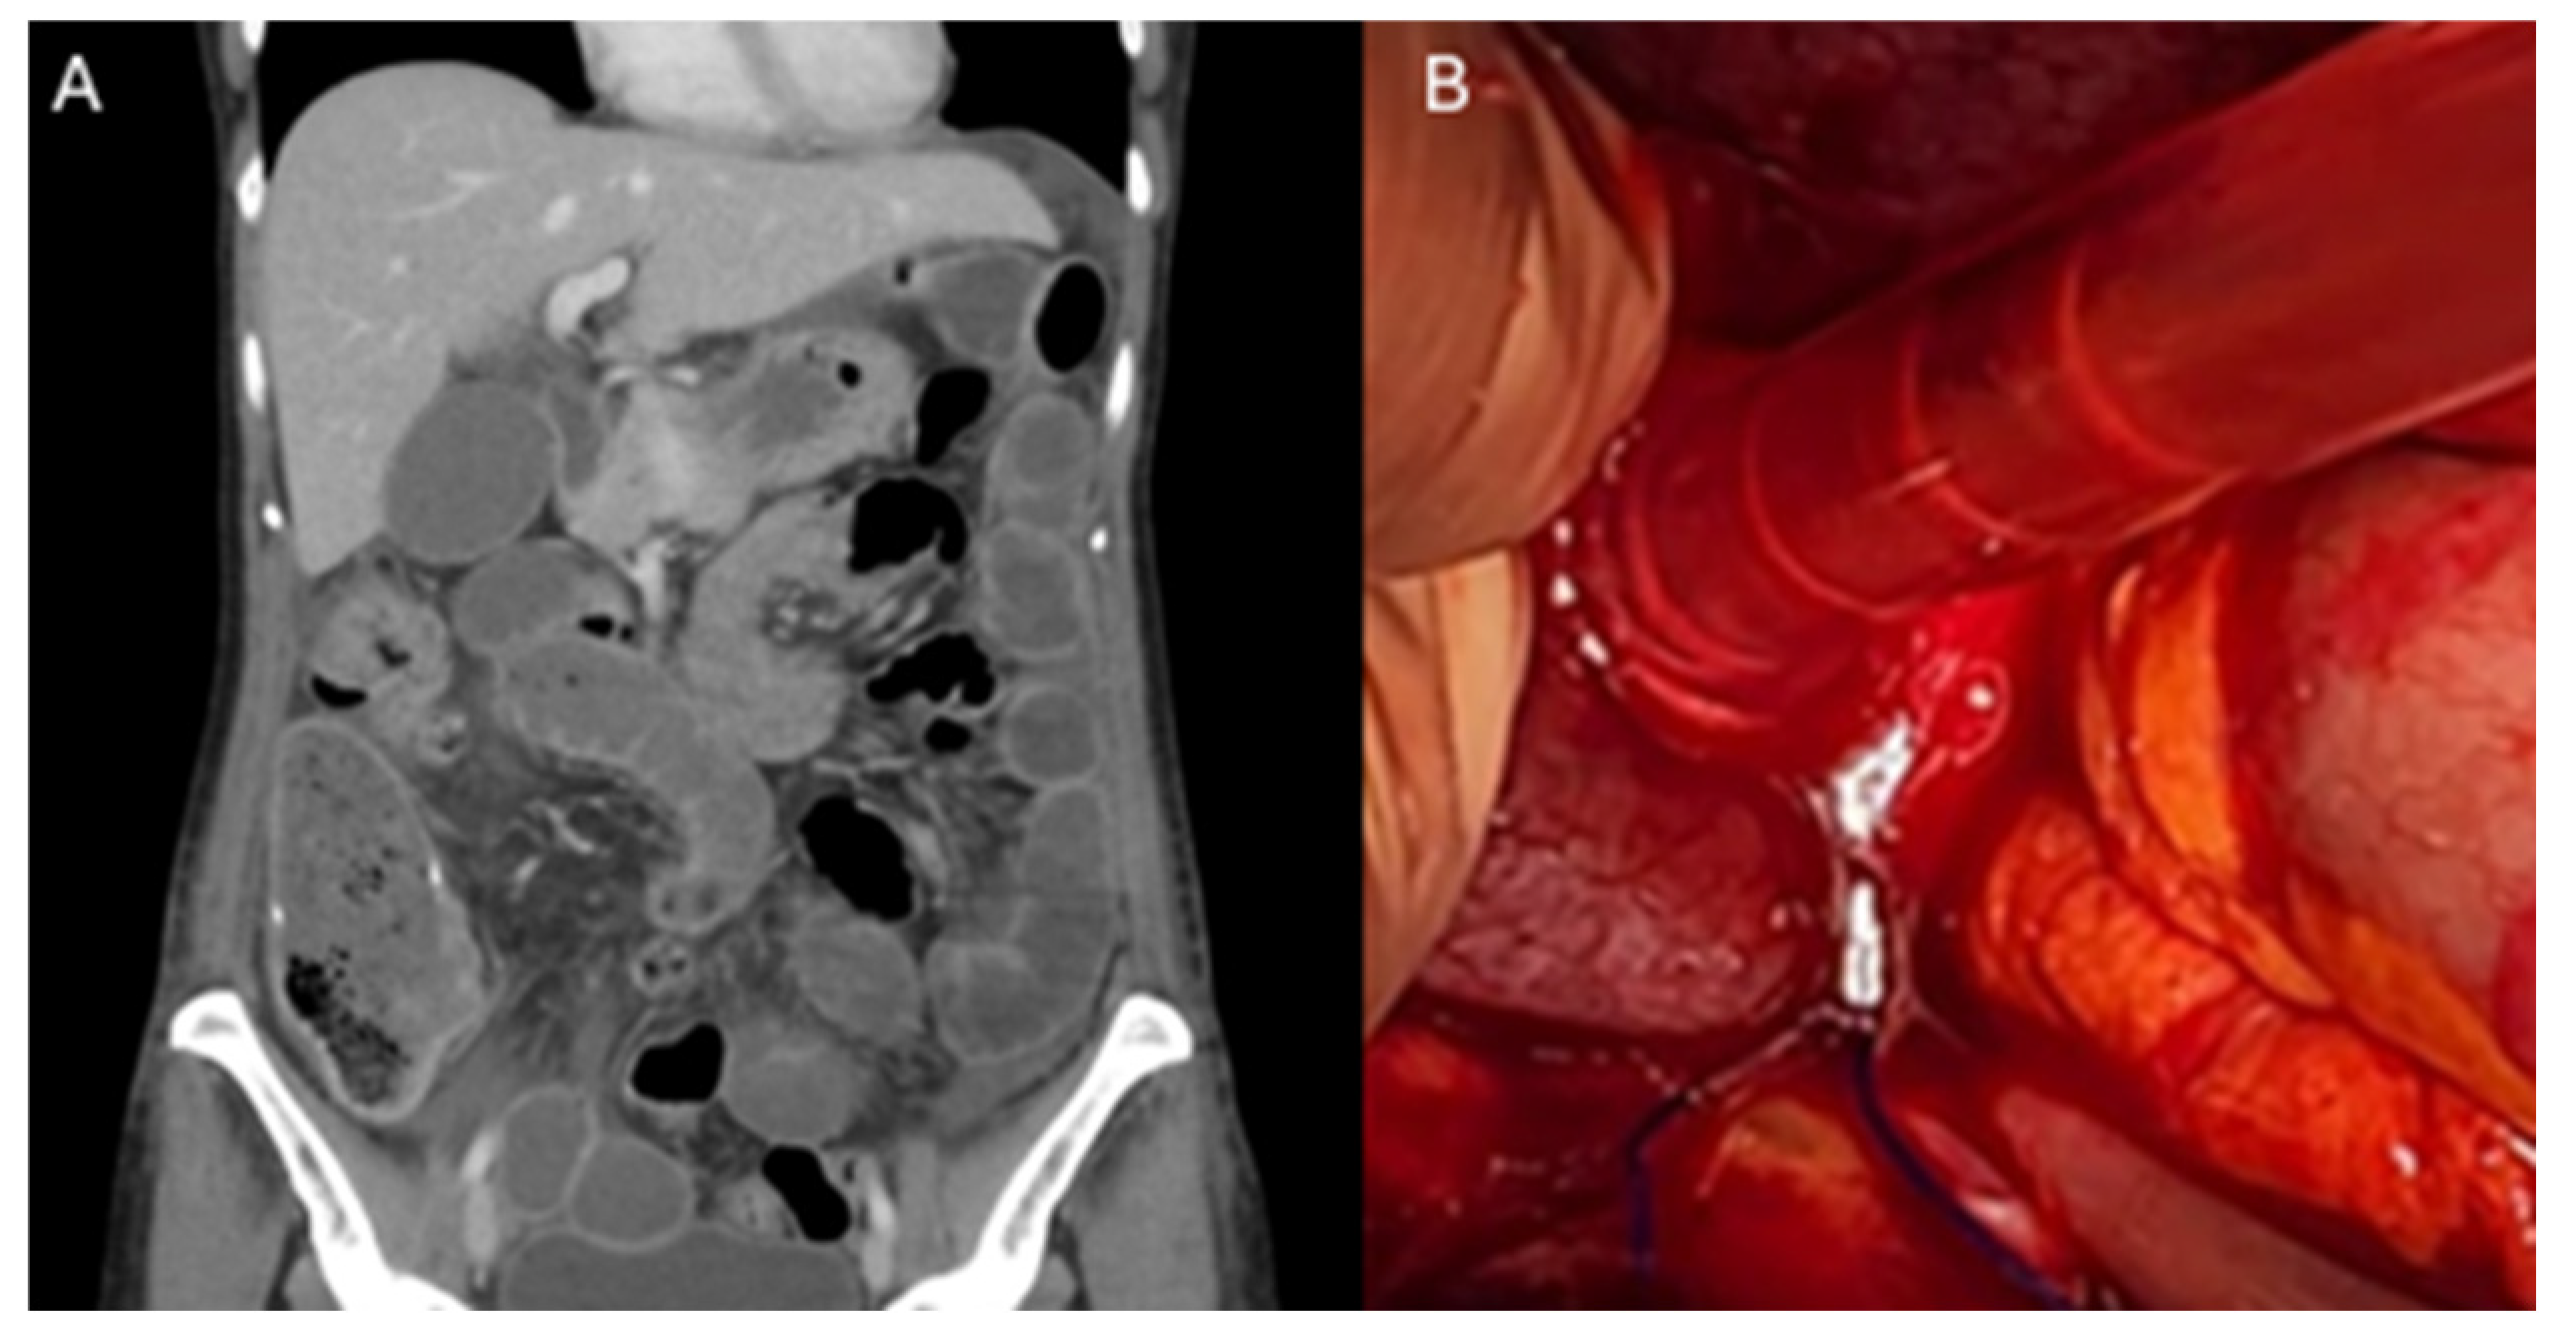

| Pajtak et al. [19] | 1 | Robot-assisted laparoscopic sacrocolpopexy | V-LocTM (Covidien, Mansfield, MA, USA) | 42 days Nausea, vomiting | Ischaemic small bowel adherent to the barbed suture | Diagnostic laparotomy and small bowel resection | 7 days |